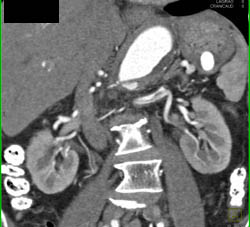

Splenic Artery Aneurysm